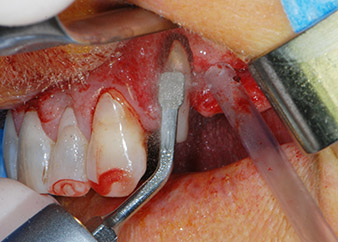

Въпреки това, ние се придържахме към първоначалния си план да запазим и двата зъба като абатмънти за временен мост по време на 6-месечната остеоинтеграция на имплантите. При повторна интервенция, ситуацията трябва да се преразгледа. Първо, в опит да се овладее ендо-перио проблема, останалата повърхност на зъба е внимателно обработена с пиезохирургично оборудване (Piezomed, W&H, използван с накрайник S1 под формата на шпатула, първоначално проектиран за ерозия на латералната синусна стена) (Фиг. 4).

След това апексът се изпилява със същия инструмент, за да се отстрани остатъчната инфектирана апикална тъкан и да се намали възможното допълнително усложнение по кореновите канали (апикоектомия) (Фиг. 5). Ретроградно запълване не е необходимо, защото ортоградното запълване току-що е ревизиран.

Благодарение на прецизното и надеждно изпълнение, периодонталното отстраняване и апикоектомията на място 24 са изпълнени с апарат за пиезохирургия (Фиг. 19). За да се избегне рискът от загуба на зъба, необходимо е цялостно почистване, но без да се упражнява твърде голям натиск. Апаратът беше много полезен при изпиляване на костта в хирургичното поле, което работи много добре с оглед на специфичния ефект на кавитация и режещите характеристики на новата технология.